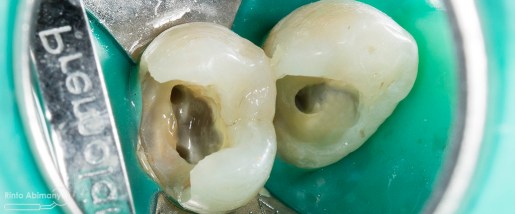

Pertama saya lakukan anestesi infiltrasi dan kemudian memasang rubber dam untuk isolasi daerah kerja, dilanjutkan pembersihan karies dan pembukaan kamar pulpa.. Pada kasus ini pengerjaan dilakukan langsung pada dua gigi…

Setelah akses ke kamar pulpa didapat, lalur dirapihkan agar arah masuk file dapat lurus, maka selanjutnya adalah proses cleaning and shaping… Panjang kerja diukur menggunakan apex locator Root ZX mini (Morita) dan preparasi saluran akar menggunakan i3 Gold (Denjoy)… Irigasi memakai larutan NaOCl 5,25% dan diaktivasi menggunakan waterpik dan tip endoactivator…

Setelah proses cleaning and shaping dilakukan trial gutta percha untuk melihat apakah kon utama yang akan kita gunakan pas dengan saluran akarnya…

Setelah melihat hasil ronsen trial guttap maka pengisian siap dilakukan… Untuk pengisian saluran akar saya memakai tehnik warm vertival condensation memakai alat Element Obturation Unit (SybronEndo) dan siler AH plus (Dentsply)…

Setalah pengisian usahakan kamar pulpa dibersihkan dari sisa2 siler dan kotoran2 agar bahan adhesive yang kita pakai untuk restorasi dapat melekat maksimal.. Untuk basis saya menggunakan X-tra Base (Voco) kemudian diatasnya memakai komposit Z 350 XT (3M)…